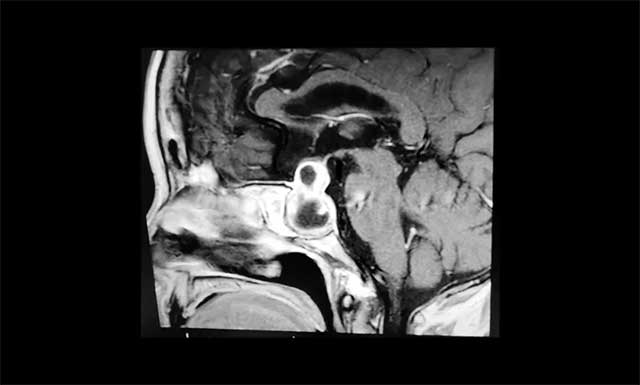

鞍區(qū)MRI平掃+增強顯示:蝶鞍顯著擴大,鞍區(qū)見不規(guī)則囊實樣腫塊,大小約2.6*2.1*3cm,視交叉上抬,鞍上池受壓,侵及雙側(cè)海綿竇,蝶竇結(jié)構(gòu)紊亂,臨近鞍底下陷、部分骨壁缺失。

▲ 腫瘤向鞍內(nèi)、鞍上、鞍旁發(fā)展,呈“啞鈴形”

李士其教授分析:腫瘤主體位于鞍內(nèi)、鞍上、鞍旁發(fā)展,呈“啞鈴”形。從影像學(xué)資料上看,發(fā)現(xiàn)瘤體已經(jīng)非常大了,屬于巨大垂體瘤。瘤體占據(jù)鞍區(qū),并向蝶竇和鞍上發(fā)展,侵襲雙側(cè)海綿竇,視神經(jīng)、視交叉受壓,所以需要馬上進行手術(shù)切除,解除壓迫。若任其發(fā)展,將來有失明的風(fēng)險。